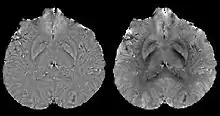

COSMOS solves the inverse problem by oversampling from multiple orientations.[11][12] COSMOS utilizes the fact that the zero cone surface in the Fourier domain is fixed at the magic angle with respect to the B0 field. Therefore, if an object is rotated with respect to the B0 field, then in the object's frame, the B0 field is rotated and thus the cone. Consequently, data that cannot be calculated due to the cone becomes available at the new orientations.

COSMOS assumes a model-free susceptibility distribution and keeps full fidelity to the measured data. This method has been validated extensively in in vitro, ex vivo and phantom experiments. Quantitative susceptibility maps obtained from in vivo human brain imaging also showed high degree of agreement with previous knowledge about brain anatomy. Three orientations are generally required for COSMOS, limiting the practicality for clinical applications. However, it may serve as a reference standard when available for calibrating other techniques.